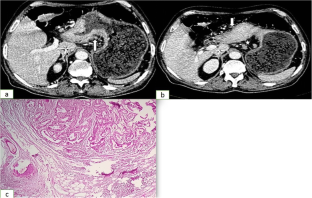

Fig. 4